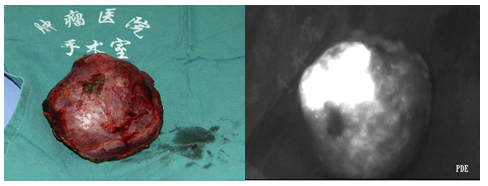

有了 ICG熒光造影劑,在進行解剖性肝切除過程中,通過對目標肝段門靜脈穿刺,可使目標肝段進行確切持久的染色;或者對除目標肝段外的肝段進行反染色,借助熒光信號的對比,可以明確目標肝段的準確邊界,提高了規(guī)則性肝切除的準確度,可以幫助醫(yī)生徹底清除肝內微小轉移灶,并避免殘肝缺血。

ICG熒光顯像技術是通過吲哚菁綠(ICG)完成血管造影后,應用熒光探測設備,探測ICG發(fā)出的不可見熒光,經過整合后輸出肉眼可視圖像。

熒光顯像技術等可視化技術的發(fā)展和進步,延伸了外科醫(yī)生的眼睛,促進肝癌外科治療理念從不規(guī)則肝切除走向精確解剖性肝切除,利用這些可視化技術,可以使外科醫(yī)生更加精確地實施手術,減少對肝臟的損傷,降低術后并發(fā)癥的發(fā)生,使個體化精細化的手術切除方案成為可能。

濱松PDE系列中目前主力型號是pde-neoII,是一款以濱松公司的弱光探測技術為基礎的熒光顯像設備,在外科多科室廣泛應用,其中在肝膽外科不僅應用于術中肝段顯像,在腫瘤邊界界定、切緣的確定、微小病變或轉移病變檢測方面也有廣泛的應用。